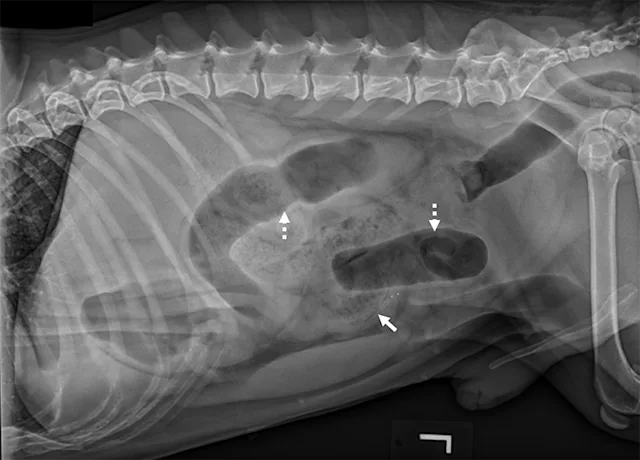

Left lateral image showing segmental dilated gas-filled intestines (dashed arrows) with heterogeneous soft tissue in a small intestinal segment (solid arrow) in a dog. The foreign material was cloth, and the diagnosis was small intestinal mechanical obstruction. Exploratory laparotomy was performed.